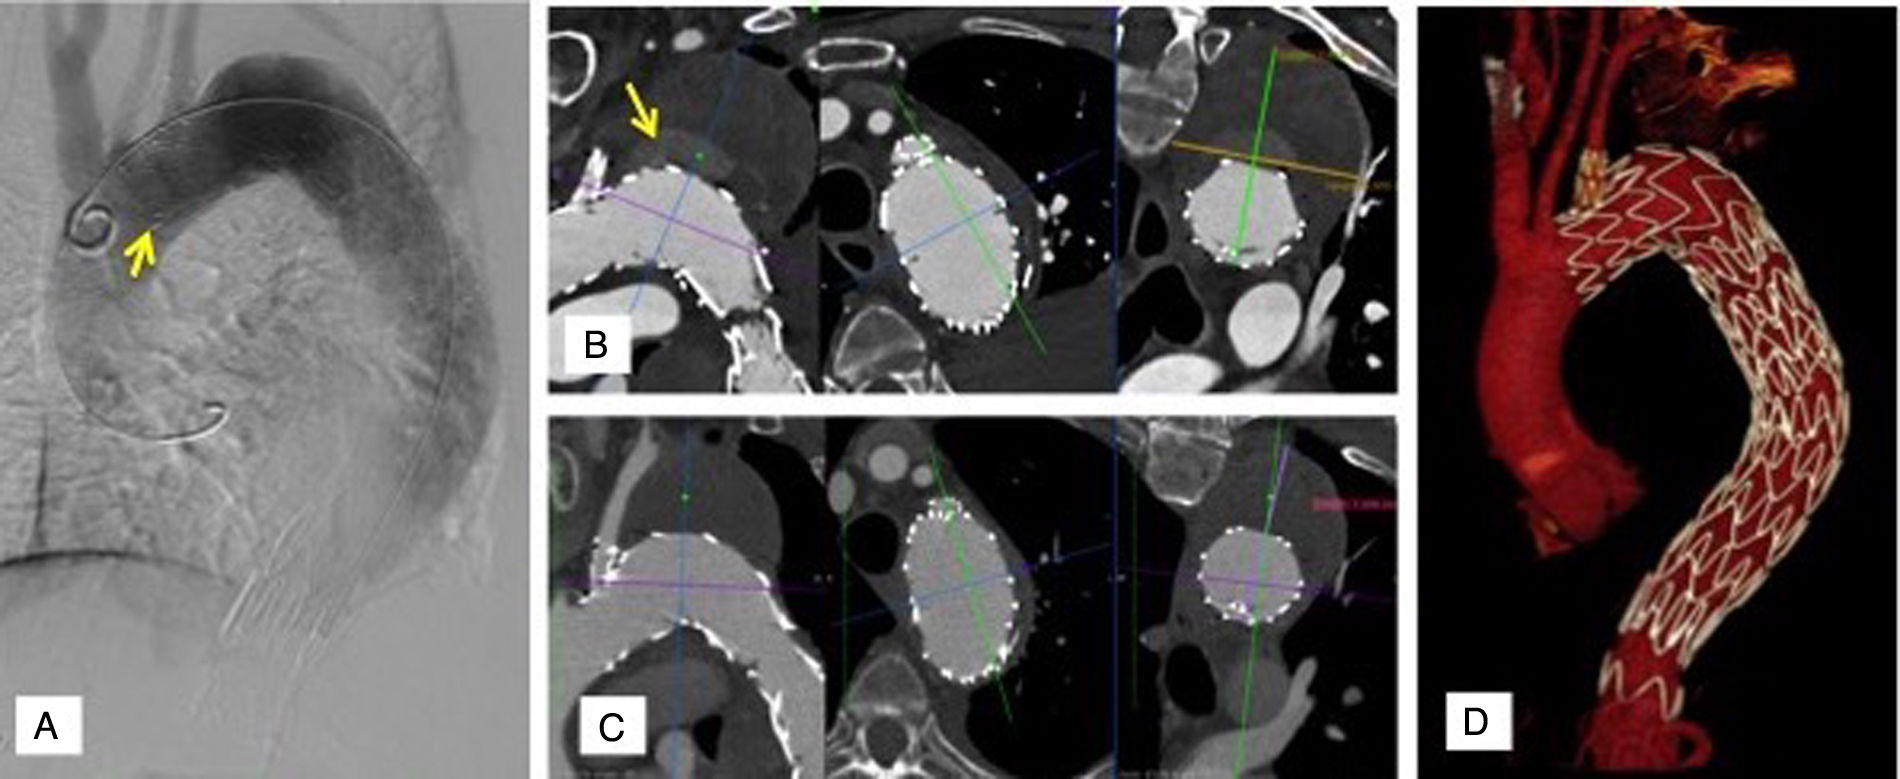

Se realizaron procedimientos concomitantes planificados en 3 casos. Se optimizó una fenestración del septo con balón 12mm previo a endoprótesis fenestrada para facilitar el acceso a la arteria renal derecha (caso 4). Se colocó un stent cubierto en arteria iliaca común derecha por aneurisma sacular de la misma (caso 5). Se embolizó con coils una rama anómala mediastínica de la ASI en zona de sellado de rama ASI, así como se extendió distalmente rama ASI por irregularidades de diámetros (fig. 5).

Procedimientos endovasculares adicionales: Caso 4: Disección tipo B crónica, estadío torácico previo a F/BEVAR. A) Tomografía axial computarizada preoperatoria. Fenestración (flecha) calcificada en septo correspondiente a ostium original de arteria renal derecha. B) Fusión para marcaje de ostia viscerales y fenestración de septo. Uso IVUS (flecha corta) para comprobar guía en FL (flecha larga). C) Angioplastia con balón 12×20mm (flecha larga) sobre guía Rosen 0,035” cruzando de VL a FL (flechas cortas) a nivel de fenestración de septo para optimización de la misma. Caso 5: D) Origen anómalo (flecha) de vaso mediastínico a 1cm de ostium ASI. E) Extensión distal de rama ASI con Gore® Viabahn® VBX stent balón-expandible 11/39mm (flecha). F) Embolización con coils de rama mediastínica (flecha corta), extensión de rama ASI con stent cubierto (flecha larga). ASI: arteria subclavia izquierda; FL: falsa luz; F/BEVAR: fenestrated/branched endovascular repair; IVUS: intravascular ultrasound; VL: verdadera luz.